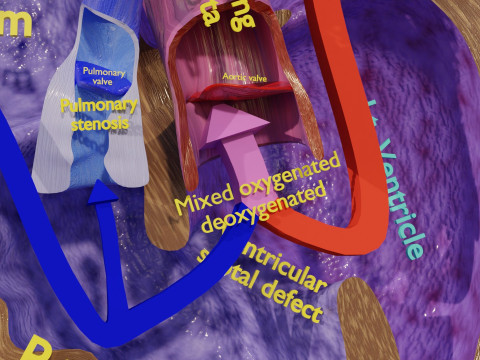

The model meshes include adult circulation versus circulation in Tetralogy of Fallot (TAF), arrow labels and text labels. The blood flow in a patient with Tetralogy of Fallot is outlined in this model. To contrast it to normal blood circulation a separate model of normal circulation is included. The Tetralogy of Fallot (OVER RIDING OF AORTA, PUL STENOSIS, VENTRICULAR SEPTAL DEFECT, RIGHT VENTRICULAR HYPERTROPHY), fossa, ligament teres , venosus, and arteriosus are duly depicted with proper labelling and blood flow directional arrows. Excellent model for teaching, demonstration and knowlegde of human body. The models include both procedural and image textures blend files separately. The texture file include diffuse, roughness and normal png and jpeg based on non overlapping UV maps.